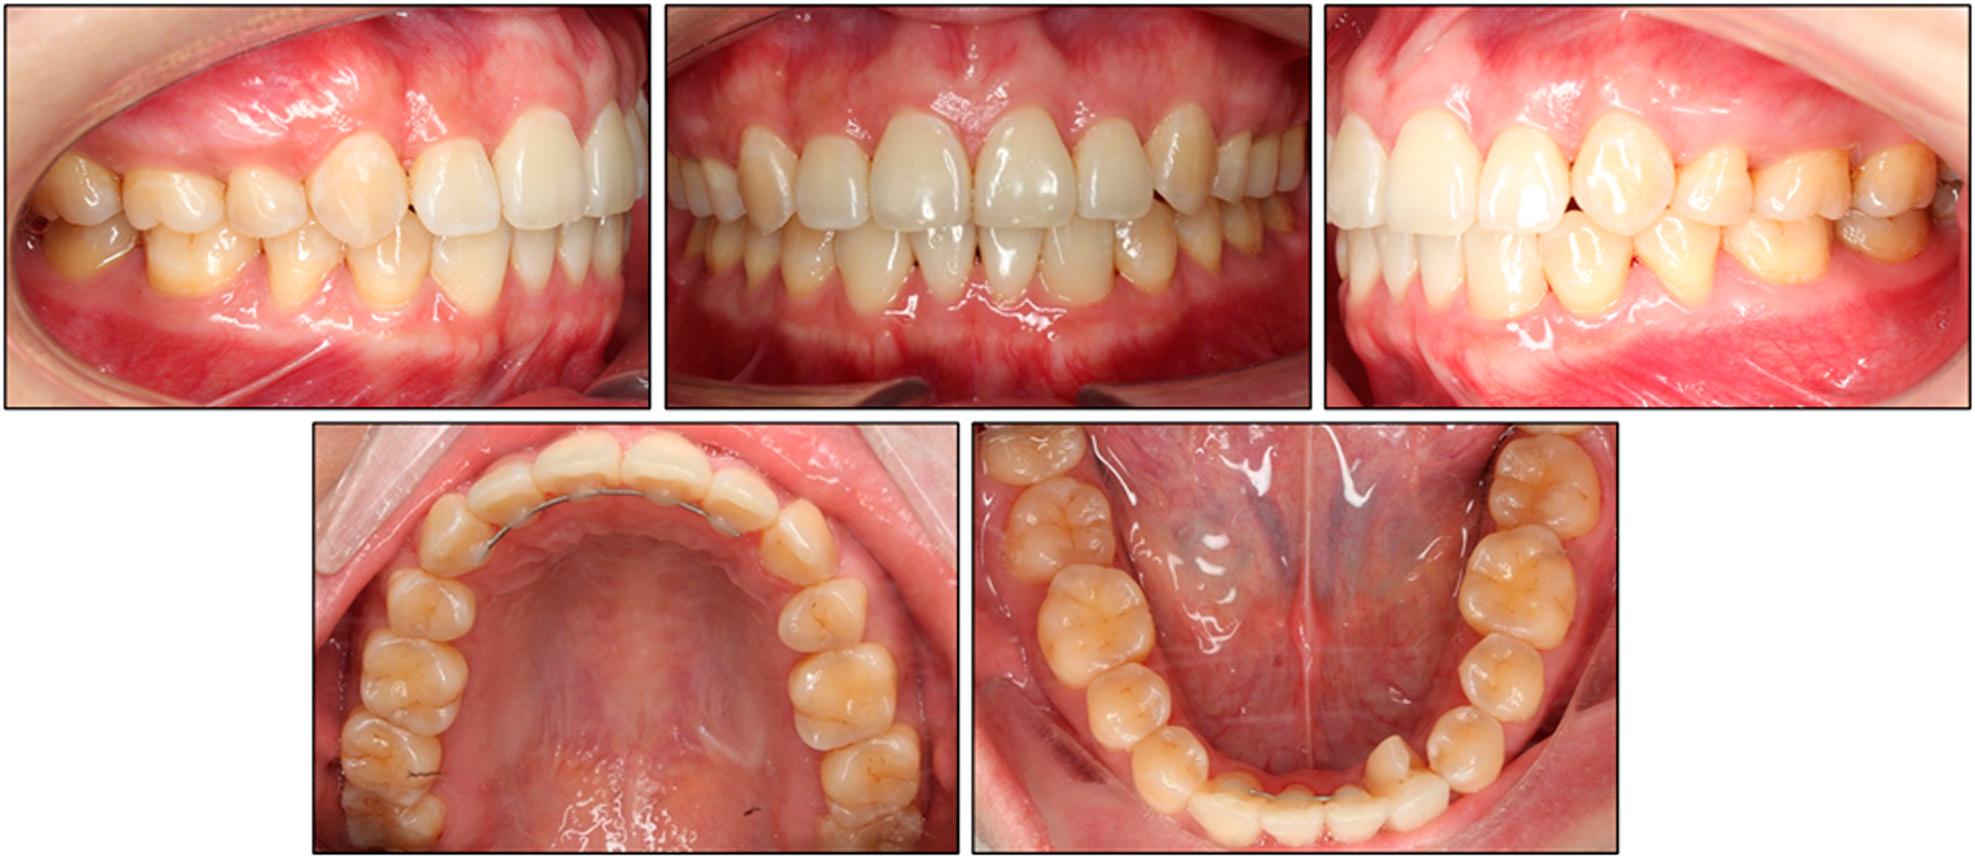

An intra-oral inspection revealed severe maxillary crowding with a 10.8 mm arch-length deficiency (Figure 2). The mandibular arch displayed mild crowding of 2.8 mm, and only four anterior teeth were present. On the left side, an enlarged bifid crown with a pronounced developmental groove was noted, suggesting incomplete fusion of the lateral incisor and canine. On the right side, a single, bulky crown larger than a normal canine and lacking any separation suggested complete fusion of the same tooth pair. Angle molar relationships were Class I bilaterally, and the fused “canine” units also occluded in Class I relationships. The maxillary dental midline co-incided with the facial midline, whereas the mandibular midline deviated 2 mm to the patient’s right.

Pretreatment maxillary and mandibular study models.